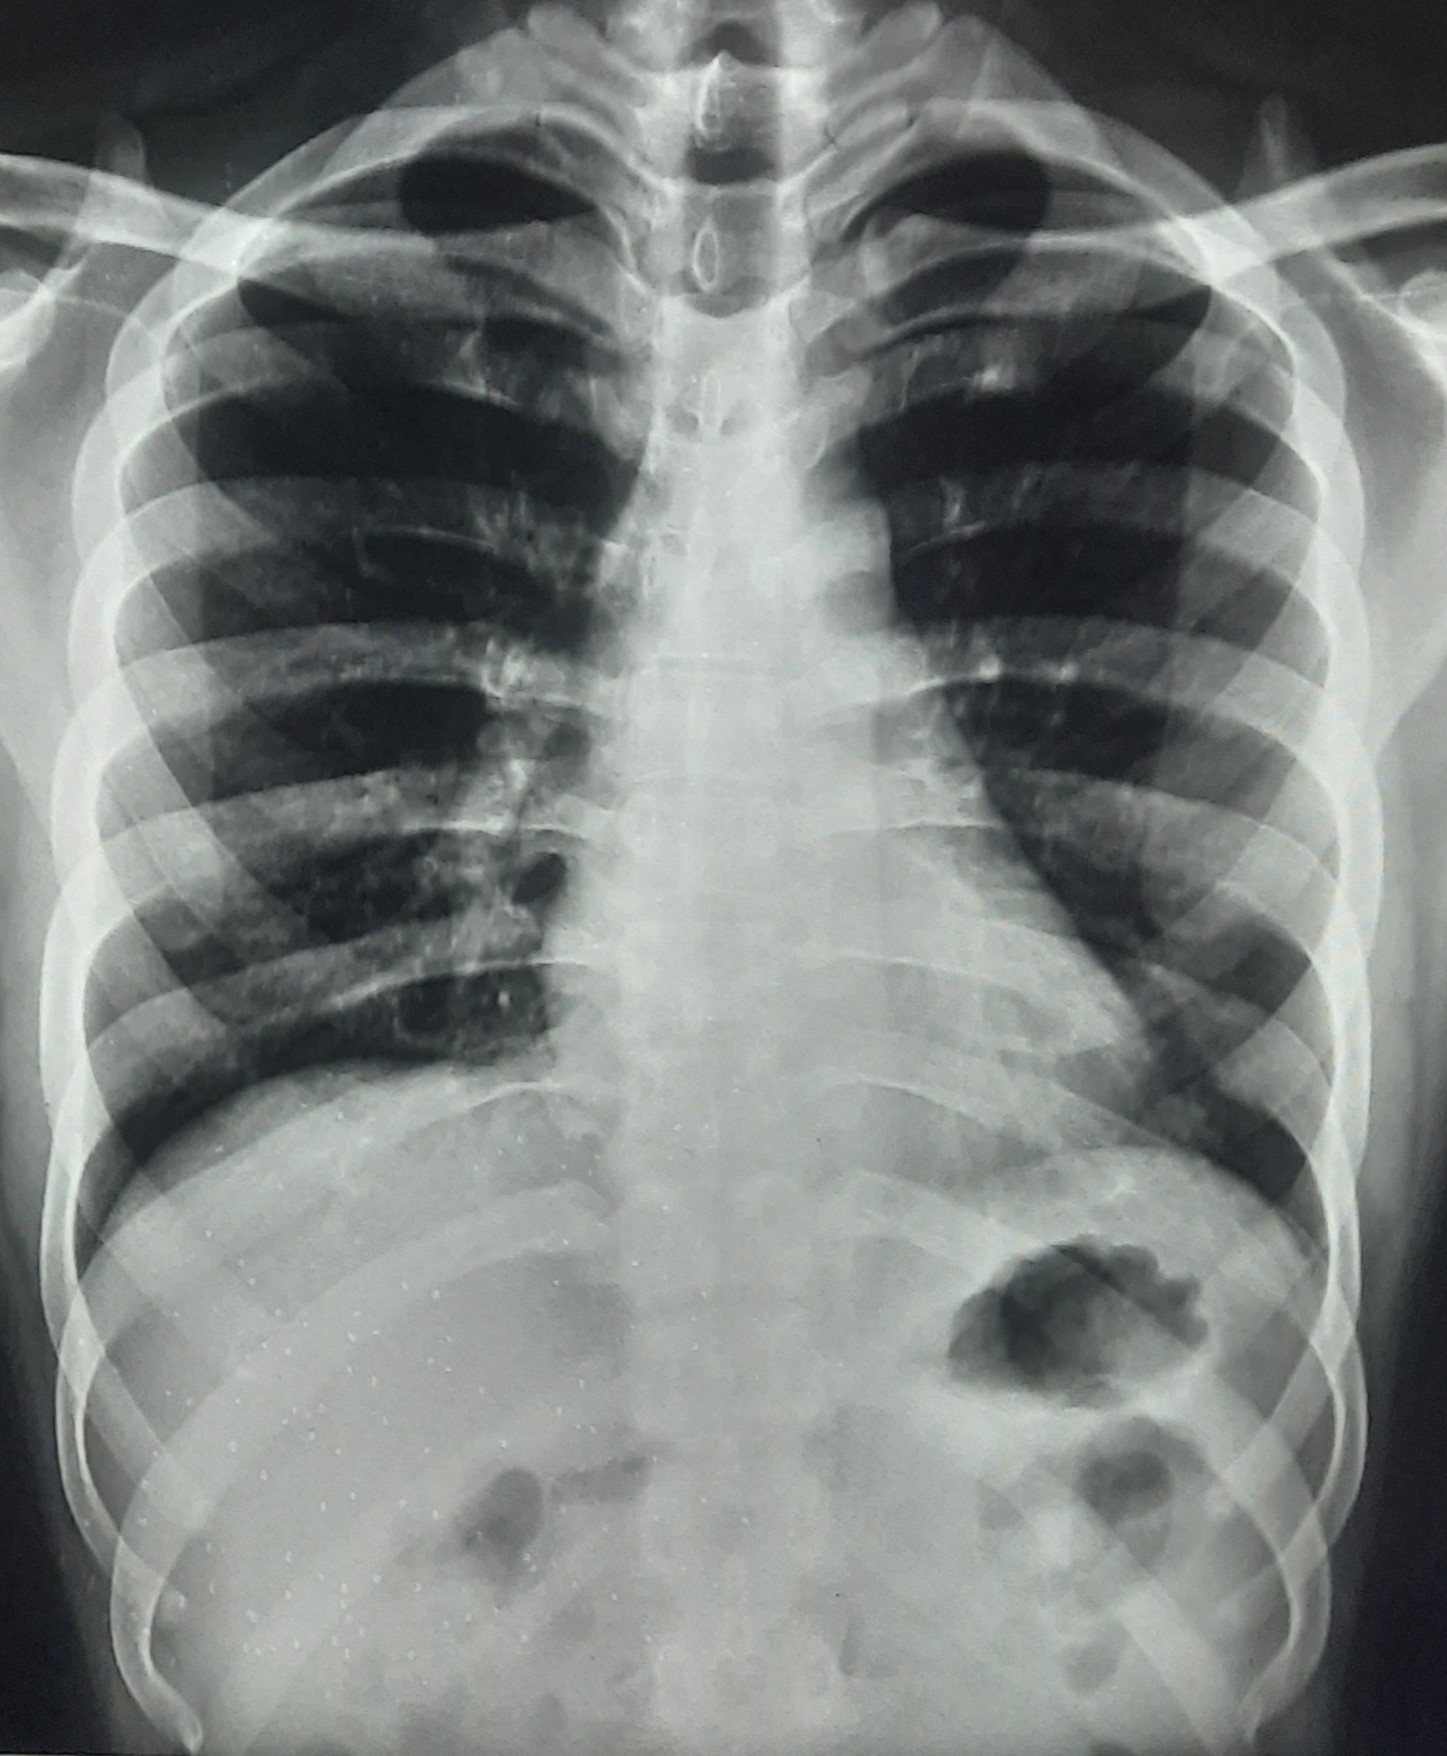

| 318 | IGGMC, Nagpur, Nagpur | P2 | 29-4154 | Tahera Bee | Consent taken on Paper | 70 Yrs. |

Provisional Diag : Post TB Bilateral Bronchiectasis

Final Diag : Post TB sequalae, Bilateral Bronchiectasis In Lower Lobe With Type 1 Respi Failure With Sepsis With Septic Shock With SYST HTN |

Post TB Sequelae | Abnormality visible on x-ray |